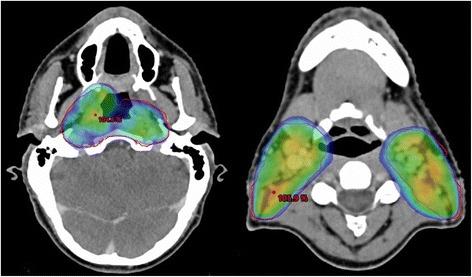

Patient was first diagnosed with locoregionally advanced, non-keratinizing nasopharyngeal carcinoma in 2010. After achieving complete remission following induction chemotherapy and concurrent curative chemoradiation, the patient subsequently developed distant and locoregionally recurrent disease. He received various treatments (neck dissection, radiotherapy to a bony metastasis, palliative chemotherapy, stereotactic re-irradiation of local recurrence) before initiation of anti- PD-1 immunotherapy with pembrolizumab in January of 2016. Following marked local progression 6 months thereafter, we performed re-re-irradiation of the recurrent tumor after careful evaluation and treatment planning. While treatment was well tolerated, the patient subsequently developed marked clinical and radiological signs of immunostimulation with mucosal irritation and swelling of lacrimal and salivary glands as described in the report. Immunotherapy with pembrolizumab was reinitiated, with re- staging showing excellent response with regression of all tumorous lesions. At the time of this report, following near complete recovery of inflammatory symptoms, the patient remains in excellent condition and free from recurrence under treatment with pembrolizumab.

患者于 2010 年首次诊断为局部晚期、非角化性鼻咽癌。在诱导化疗和同期根治性放化疗后达到完全缓解后,患者随后出现远处和局部复发疾病。在 2016 年 1 月开始接受抗 PD-1 免疫疗法帕博利珠单抗治疗之前,他接受了各种治疗(颈部清扫术、骨转移放疗、姑息性化疗、局部复发立体定向再放疗)。6 个月后局部进展明显,我们在仔细评估和治疗计划后对复发性肿瘤进行了再放疗。虽然治疗耐受性良好,但随后患者出现明显的免疫刺激临床和影像学迹象,如报告所述的黏膜刺激和泪腺及唾液腺肿胀。重新开始使用帕博利珠单抗免疫治疗,重新分期显示所有肿瘤病变均有极好的反应,完全消退。在本报告时,在炎症症状几乎完全恢复后,患者在帕博利珠单抗治疗下状况良好,无复发。